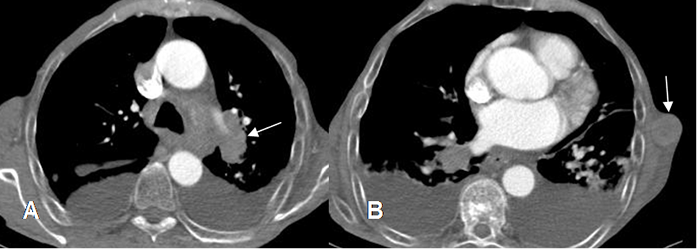

Fig 220 A. Metástasis muscular.

A: TAC axial en ventana de tejido y B: en ventana ósea. Neoplasia pulmonar con adenopatías peritraqueales. Existen metástasis en los tejidos blandos, en relación con el músculo subescapular izquierdo (Flechas delgadas) y lesión lítica costal derecha. (Flechas gruesas).